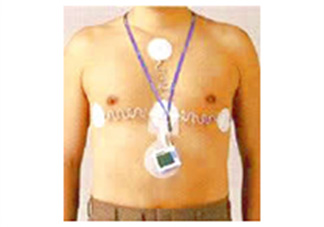

貧血、炎症、肝臓・腎臓の状態、糖尿病、ホルモンバランス、アレルギー、感染症の有無などを調べます。 - 心電図・24時間心電図(ホルター心電図)

動悸や息切れ、胸の違和感の原因となる不整脈や心臓の異常を確認します。

日常生活中の心電図を記録することで、通常の検査では見つかりにくい異常も調べることができます。 - レントゲン・CT・MRIなどの画像検査

生理検査

一般の心電図の弱点は実際の記録時間が短い事です。そのため、一過性の不整脈や狭心症をたまたまキャッチできるというチャンスは滅多にありません。そんな短時間しか記録できないという欠点を補うのが超小型24時間心電図(ホルター心電図)です。小型のホルター心電図は24時間心電計を装着して丸1日心電図を撮り続ける検査です。一般の心電図とは違い、24時間連続記録するため、通常では発見されにくい一過性の症状の診断に有用です。